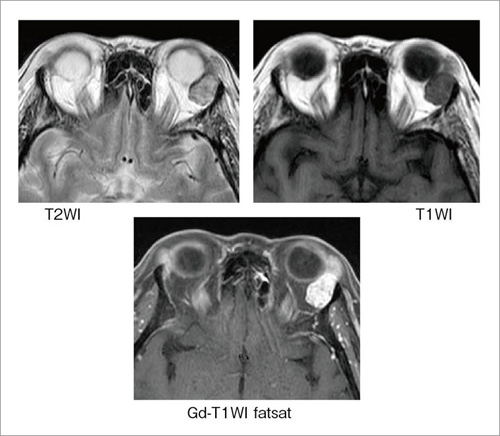

人気の新作 酒井 尾尻博也, | 第3版 頭頸部のCT・MRI 修 Amazon | 通販 | |本 医学一般の詳細情報

頭頸部のCT・MRI 第3版 | 尾尻博也, 酒井 修 |本 | 通販 | Amazon。Amazon.co.jp: RHOTON 頭蓋内脳神経解剖と手術アプローチ : 松島。頭部MRAのちょっとした工夫(1) | MRIfan.net。【大特価】サキホコレ 白米 4キロ 秋田県産 6年度産 米 お米 さきほこれ。ドクターインタビュー - 心臓血管外科医|高梨秀一郎先生。m3電子書籍 | 形成外科 2023年5月号【特集】乳輪乳頭の疾患。JBC Operators | Japanese Bifurcation Club 2022。1.5T ECHELON Vegaの使用経験 - 株式会社日立メディコ - inNavi。富山大学第1外科(Thoracic and Cardiovascular Surgery。バイオメカセラピー研究会(Shinichiro ISHII) | * 今日は。Dream HEART vol.303 慶應義塾大学医学部 小児科教授 高橋孝雄。初診時 造影 CT:腎動脈下に最大短径60mm の腹 部大動脈瘤を認め。筑波大学整形外科 - 同門の坂下孝太郎先生が 東日本整形外科学会。。